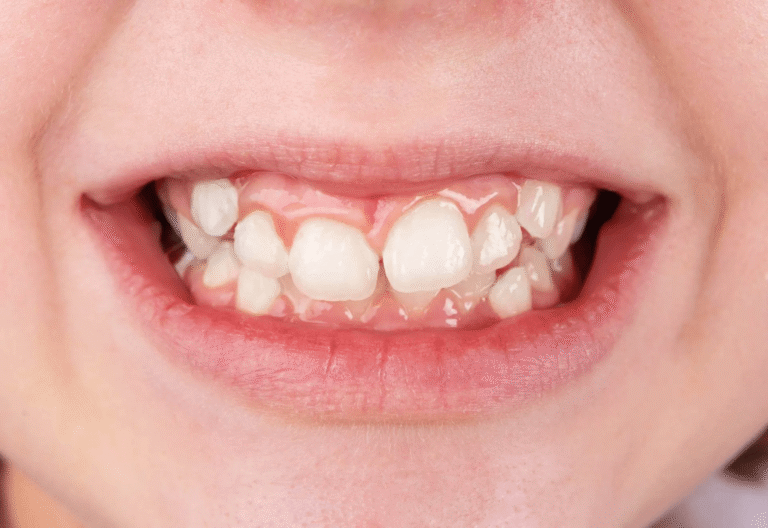

Скупчени зъби

Това е състояние, което се получава, когато няма достатъчно място в устата за всички зъби. Липсата на достатъчно пространство води до припокриване, изкривяване или избутване на зъбите напред или назад. Скупчените зъби често са в резултат на прекалено големи зъби, преждевременна или късна загуба на млечни зъби или недостатъчно пространство в челюстта.

Усложнения, които могат да настъпят – При скупчени зъби добрата орална хигиена е много по-трудна и това увеличава риска от кариес и заболявания на венците. Липсата на лечение води до неравномерно износване на зъбите, което от своя страна води до износване на емайла и чувствителност.